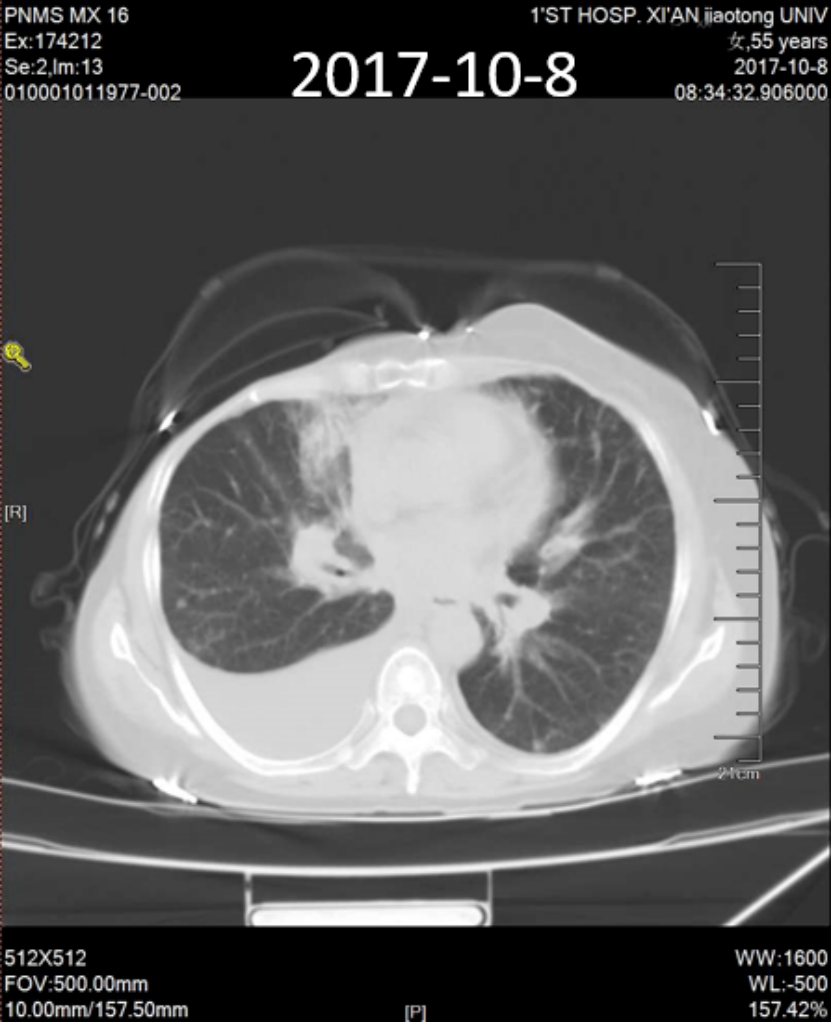

辅助检查:胸部CT(2017年10月8日)示:右乳术后,右上肺前段实变,右侧胸水(图1)。

图1:胸部CT(2017年10月8日)